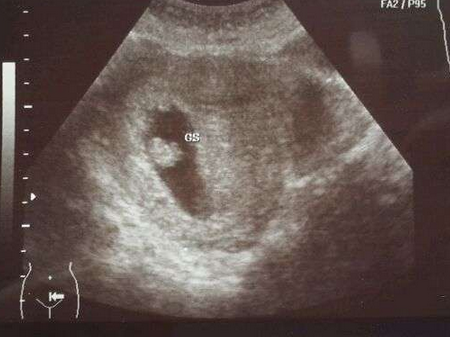

怀孕第6周胎儿长到0.85厘米,胎儿头部、脑泡、额面器官、呼吸、消化、神经等器官分化,通过B超可以清晰的看见胎囊,并能见到胎芽及胎心跳。所以,怀孕6周可以看到胎心胎芽。

怀孕第6周,一般是可以通过B超看到胚芽了,此时胚芽大小在0.5-1厘米左右,形状像个小海马。但是别看他小,胎儿头部、脑泡、额面器官、呼吸、消化、神经等器官都已经开始发育了。当然也有些孕妇此时是看不到胚芽的。